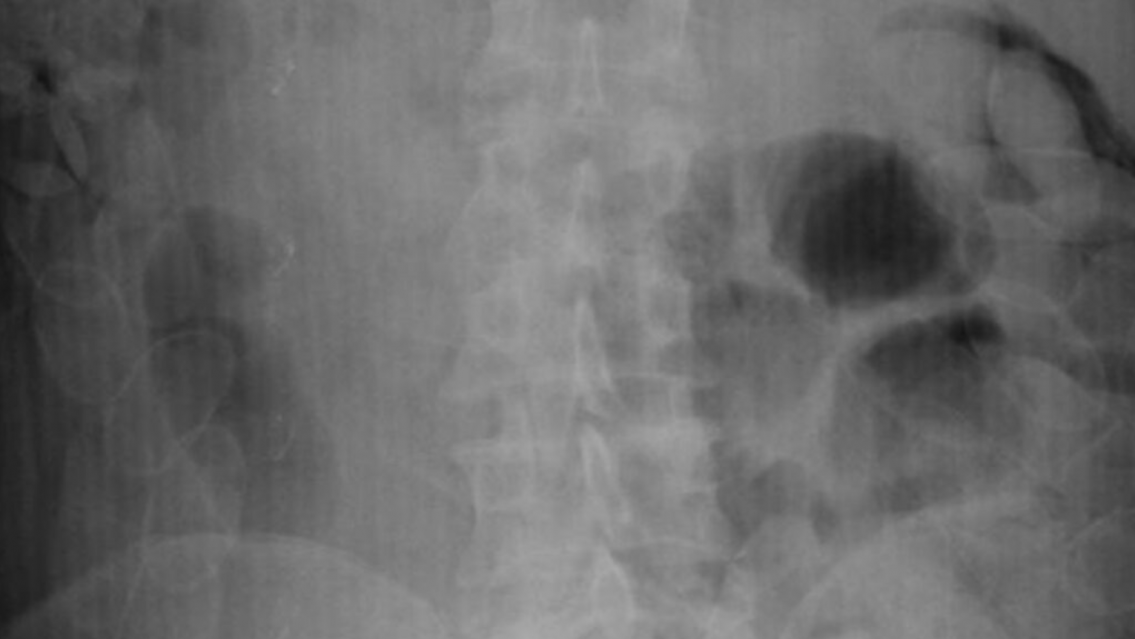

Una mujer de nacionalidad boliviana fue internada de urgencia en el Hospital Pablo Soria de San Salvador de Jujuy, luego de que se confirmara que había ingerido al menos 20 cápsulas de cocaína. El hecho ocurrió este jueves y está siendo investigado por la Justicia Federal como un posible caso de narcotráfico mediante la modalidad de "mula".

La paciente, de 45 años y con domicilio en la ciudad de Cochabamba, fue interceptada por personal de Gendarmería Nacional en Humahuaca, donde se detectaron indicios de que llevaba drogas en su organismo. Fue trasladada en una ambulancia del SAME y su ingreso al hospital se registró a las 13:56.

El diagnóstico fue confirmado por el médico de guardia del hospital capitalino, que detectó la presencia de cápsulas con estupefacientes en su interior. La mujer permanece internada y bajo estricta vigilancia de las fuerzas federales.